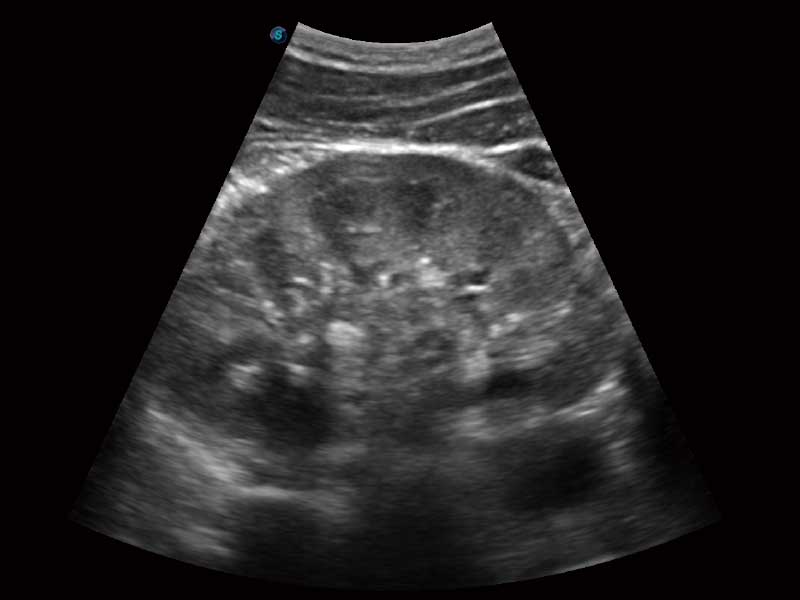

μ-Scan微米成像、空间复合成像、高分辨率血流成像。